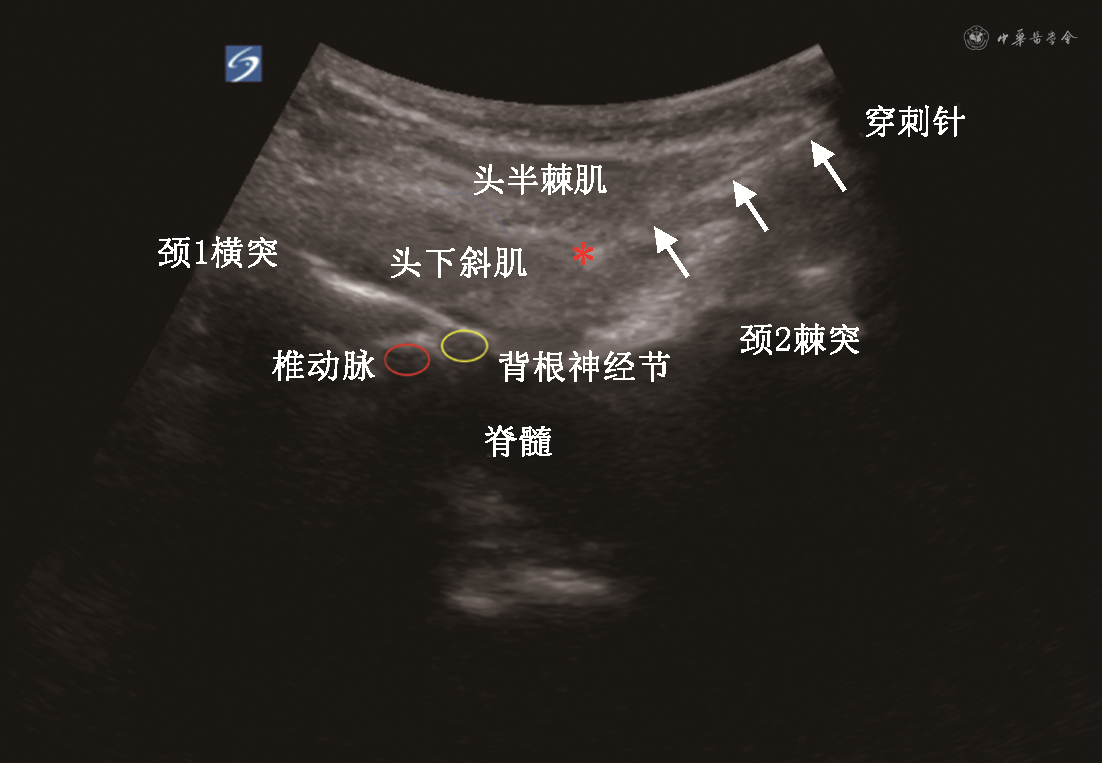

2.低温等离子消融术组治疗过程:本研究所有手术均由同一位高年资主任医师完成。入室准备,取侧卧位,患侧向上(双侧疼痛患者,严重侧在上)。常规消毒铺巾,在低频超声探头引导下,寻找头下斜肌长轴和头半棘肌平面(图1)。用长度10 mm的18 G(优尼特公司,批号207265209151-412)穿刺套管进行平面内穿刺,调整穿刺角度深度,直至到达靶点(图2),以能够完全复制患者术前疼痛特征作为确定最佳穿刺针位置的标准。行低温等离子消融术时,从穿刺套管中取出针芯,置入一次性等离子体手术刀头,选择2档进行消融,每个消融周期为30 s,共6个周期。